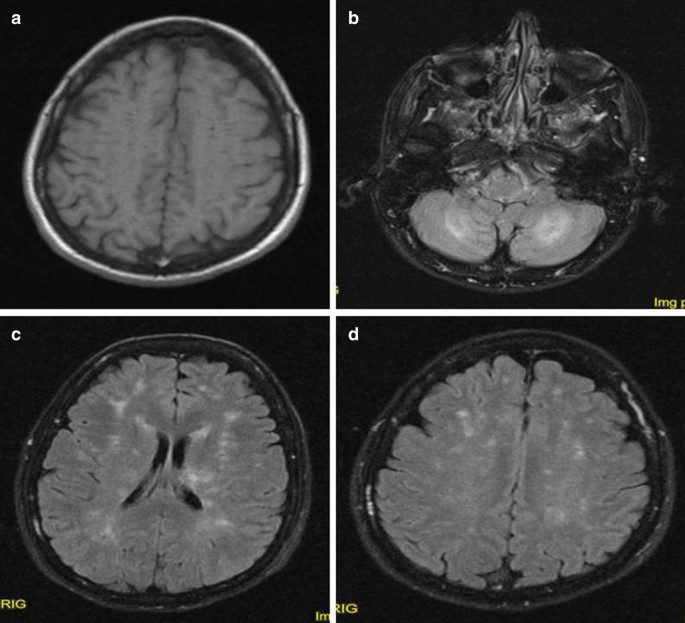

Six days after admission, the patient underwent a control CT scan, which demonstrated a partial resolution of the renal alterations suggestive of pyelonephritis. She also underwent a control brain MRI on day 9 after admission. The MRI scan showed a reduction of all the previously detected lesions, with less swelling of the thalamus and cerebellum. On the other hand, the multiple juxtacortical and periventricular white-matter lesions remained substantially unchanged, also showing some microbleeding spots (Fig. 2)

Images from the control MRI scan. a T1-weighted image without meningeal post-contrast enhancement. b FLAIR image demonstrating a reduction of hyperintense lesions in both cerebellar hemispheres. c, d FLAIR images still showing a significant bulk of hyperintense lesions involving periventricular, deep, and juxtacortical white matter

MRI examination is another peculiar issue of our case that is worth highlighting. MRI allows the detection of subtle changes in brain and meningeal parenchyma, helps in differential diagnosis, and is a useful tool to monitor complications, treatment response, and disease evolution [34,35,36,37,38]. Meningitis may be accompanied by several other alterations that are reported in a considerable number of patients: ventricular involvement, with ependymal enhancement in T1 scans, hyperintense images in T2/FLAIR imaging, and reduced diffusivity in DWI; hydrocephalus; cerebral edema; cerebritis with T2/FLAIR hyperintense lesions and a reduction of diffusion in DWI, mostly involving cortical regions and juxtacortical white matter; vascular congestion, venous thrombosis, and ischemic lesions; and subdural empyema and cerebral abscesses [34,35,36,37,38]. Our patient did display some of these alterations, such as leptomeningeal enhancement, ventricular/ependymal involvement, multiple T2/FLAIR hyperintense lesions, and multiple areas of diffusivity reduction in DWI scans. Of note, she had dramatic cerebellar involvement; cerebellitis is a rare condition in adult patients, being more common in pediatric populations [39, 40]. Moreover, although bacterial etiology is seldom reported, cerebellar inflammation is more often caused by viral infection or postinfection and autoimmune conditions [39, 40]. Although a full recovery is infrequently described in adult patients [39], she exhibited a brilliant recovery from her cerebellar symptoms in only a few weeks.